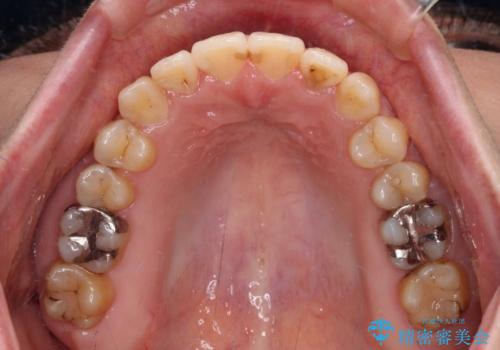

- 前歯のデコボコを気にして来院された患者様です。

前歯のデコボコはもちろん気になるところですが、舌の突出癖により上下前歯が非接触となっている状態でした。

上下前歯が非接触である開咬は、インビザラインによる治療がお勧めではありますが、しっかりと使う自信がないとのことで、ワイヤー装置にて治療を行うこととしました。

デコボコはあっという間に改善されましたが、開咬の改善に時間がかかりました。

舌の突出癖改善のトレーニングをしっかりと行っていただき、上下前歯が接触する咬み合わせを達成することができました。